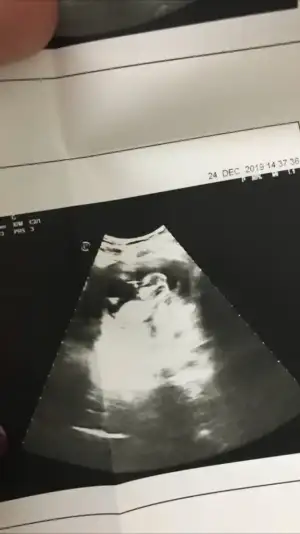

Haftam yaklaştıkça bir merak sardı.

O gözüken nub mu emin olamadım ama yine de bir atayım belki fikir yürüten olur didimm.

10+5 günlük bir kurbağa 🐸 🐣

Ne dersiniz?? Ikra meyra Ikra meyra

Net degil usg 11+ yada 12+ oldugunda paylaşın yada net varsa usg paylaşın